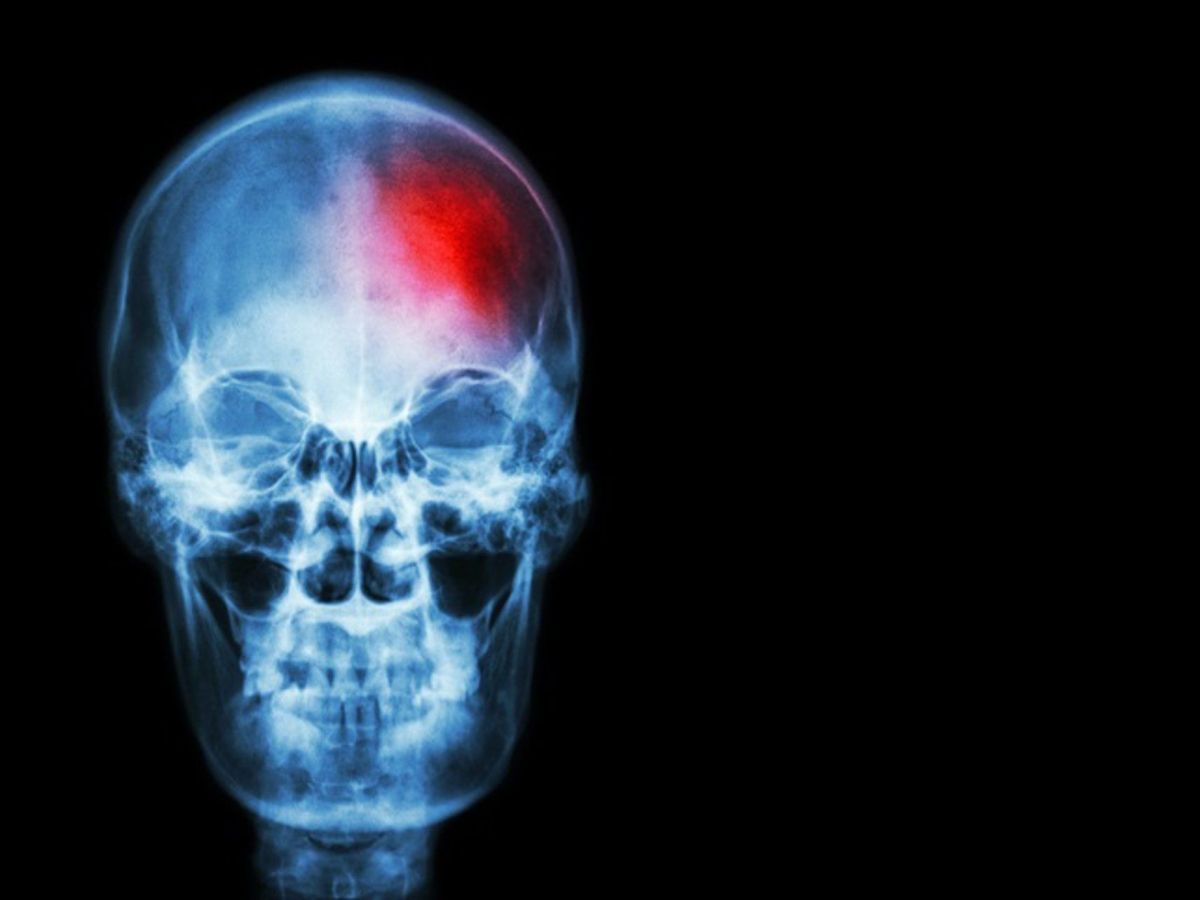

La Sociedad Española de Neurología (SEN), aprovechando la conmemoración del Día Mundial del Ictus este 29 de octubre, alerta de que el ictus representa un serio peligro para la salud pública en España. Se estima que uno de cada cuatro ciudadanos sufrirá esta afección en algún momento de su vida, siendo además una de las principales causas de muerte y discapacidad a nivel global.

«El ictus es una enfermedad cerebrovascular que se produce cuando el flujo de sangre que llega al cerebro se interrumpe o se reduce. Existen dos tipos principales de ictus: el ictus isquémico, que representa aproximadamente el 80% de los casos, y el ictus hemorrágico, que supone el 20% restante. Mientras que el ictus isquémico se produce cuando un trombo impide u obstaculiza la llegada de sangre al cerebro, el ictus hemorrágico se genera por la rotura de alguno de los vasos sanguíneos del cerebro. Pero en ambos casos el tiempo de actuación es determinante», explica la doctora Mª Mar Freijo, Coordinadora del Grupo de Estudio de Enfermedades Cerebrovasculares de la SEN.

Además, indica, «por cada minuto que pasa sin que la sangre llegue al cerebro, se pierden casi dos millones de neuronas. Por lo que si se sospecha un ictus, hay que llamar de inmediato al 112, porque solo una atención urgente puede minimizar las secuelas y salvar vidas».